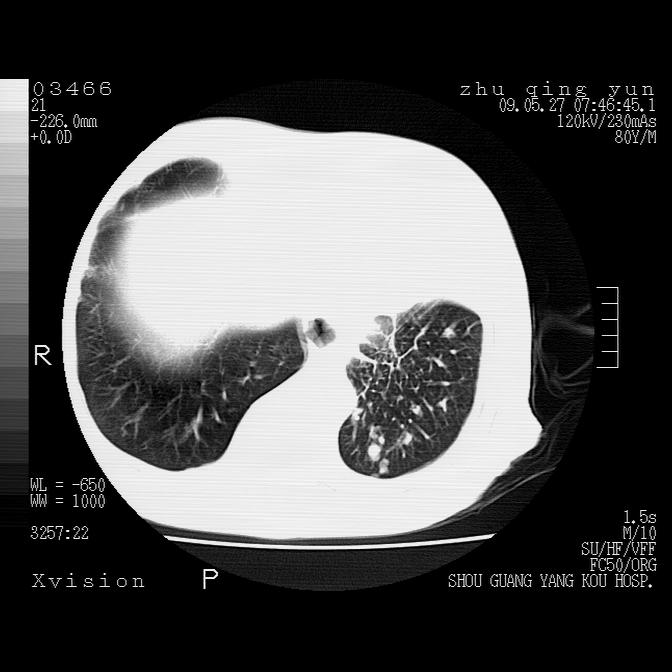

病人男性,年龄80,气喘来院,其他病史不太详细,1月前有过恶心,呕吐,在当地人民医院做过钡餐,诊断胃炎,

1)考虑左肺中央型肺癌并阻塞性肺炎,后下纵隔受侵伴纵隔淋巴结转移。2)双侧少量胸腔积液,胸膜增厚。3)心包积液。

左肺下叶见多发片状及结节状病灶,左肺基底段支气管闭塞,纵隔内见多发淋巴结肿大,纵隔向左侧移位,左侧胸廓变小。应该是左肺下叶中心型肺癌,纵隔淋巴结转移,左侧肺内转移,左肺基底段肺不张,阻塞性肺炎。

1)考虑左肺中央型肺癌并左肺下叶阻塞性肺炎、不张;左胸膜腔积液、心包积液、纵隔淋巴结转移;癌肿累及左心房。2)左心室大。冠状动脉壁钙化斑。

支持以上,左肺肿块应该是周围型吧,考虑左下肺周围型肺癌伴肺内转移,阻塞性肺炎,纵隔淋巴转移,左侧胸膜及心包转移

考虑左下肺中心性肺癌伴阻塞性肺炎,纵隔淋巴转移,左侧胸膜及心包转移。